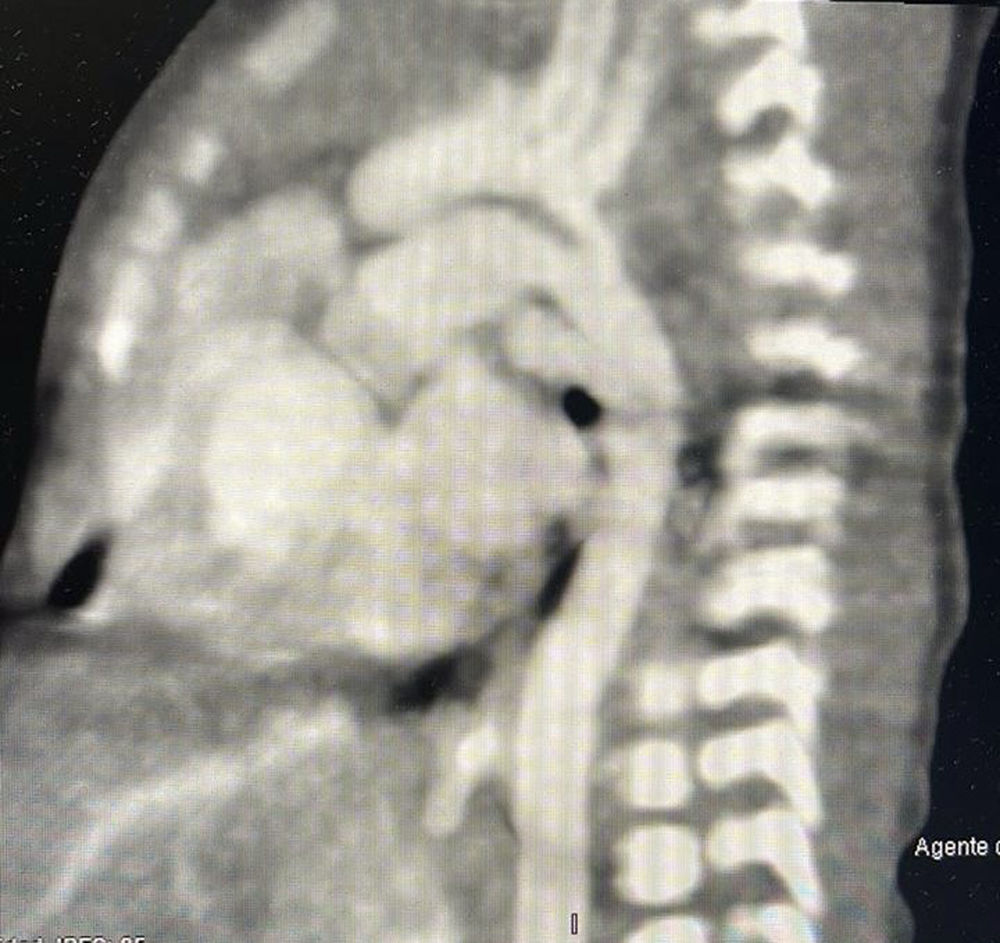

Presentación del casoPaciente neonato de 10 días de vida con el diagnóstico de canal atrio ventricular desbalanceado con vasos en malposición y coartación aórtica con valores z ligeramente disminuidos. Se presentó en sesión médico/quirúrgica aceptándose para manejo univentricular y coartectomía término/terminal ampliada con sección y sutura del conducto arterioso. Se realiza toracotomía posterolateral izquierda con disección por planos con sección de los músculos de la pared torácica hasta llegar a los músculos intercostales. Se realiza sección de pleura mediastinal con sección del ligamento de Gross, disección extensa de aorta descendente torácica, tercer tronco supraaórtico, encontrando nacimiento independiente de los ostium del segundo tronco con fusión superior tipo escopeta (figs. 1 y 2 A, 1B y 2). El tiempo de pinzamiento aórtico fue de 14min. El paciente presenta adecuada evolución con gradiente residual de 21mmHg en aorta descendente, continuando seguimiento por la consulta.

Las variaciones en los tipos del arco aórtico se describen en distintas clasificaciones, la más utilizada es la de Natsis et al.1, la cual la divide en VIII tipos, agregándose actualmente hasta XII tipos dependiendo los distintos tipos que se han encontrado6. En base a la literatura consideramos que el hallazgo transquirúrgico pudiera ser una subvariante del tronco tipo VII de la clasificación de Natsis en la cual se encuentra por separado los 4 vasos, siendo de derecha a izquierda el nacimiento de la subclavia derecha, carótida derecha común, carótida común izquierda y subclavia izquierda2. La diferencia con nuestro hallazgo es la fusión de la carótida izquierda y la carótida común derecha en la porción superior de tipo escopeta sin haberla encontrando descrita previamente en la literatura, siendo un hallazgo transquirúrgico; desconocemos si pudiera presentar alguna sintomatología, aunque consideramos que es poco probable mientras el desarrollo de los vasos y flujos sean adecuados por lo que continuara en vigilancia por nuestro servicio.